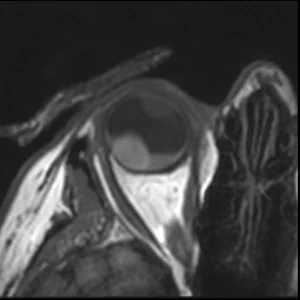

MS T2

A T2-weighted sequence with an increased in plane resolution, allowing for a better assessment of the origin of the lesion and its relation to the surrounding anatomy.

T2 OBL

Main sequence parameters:

Scan duration

01:30 min

Sequence type

Multi-slice TSE

TR/TE

1331 / 90 ms

ACQ voxelsize

0.40 x 0.42 x 2.00 mm

REC voxelsize

0.21 x 0.21 x 2.00 mm

WFS (pix) / BW (Hz)

2.25 / 193

TSE factor / shot length

17 / 180 ms

View the full sequence details.